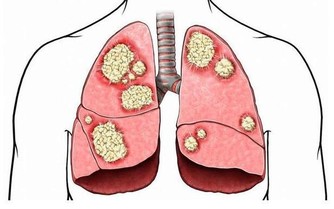

文章導讀 肝癌是一種嚴重性極大的病,肝癌病人在漫長的人生歷程中,會遇到許多挫折和磨難。眾所周知,中國的肝病患者是全世界最多的,肝癌的發病率不斷上升,在所有癌症中,肝癌的死亡率最高。

肝癌的發生並不是悄無聲息的,在肝癌發生初期,是有一定的症狀存在可以起到疾病的提示作用的。下面專家就肝癌的早期症狀做了介紹。 出血傾向:癌患者常有牙齦出血、皮下淤斑等出血傾向,主要是由於肝功能受損、凝血功能異常所致,它在肝癌合併肝硬化的患者中尤為多見。消化道出血 較為常見,主要是由於門靜脈高壓導致食管胃底 靜脈曲張 所致。事實上,消化道出血也是導致肝癌患者死亡的最主要原因。 下肢水腫:肝癌伴腹水的患者,常有下肢水腫,輕者發生在踝部,嚴重者可蔓延至整個下肢。臨床上曾見到有的患者下肢高度水腫,水液能從大腿皮膚滲出。造成下肢水腫的主要原因是腹水壓迫下肢靜脈或癌栓阻塞,使靜脈回流受阻。輕度水腫亦可因血漿白蛋白過低所致。 文章導讀

消瘦乏力:肝癌患者常較其他腫瘤患者更感乏力,此與慢性 肝炎患者相似。乏力的原因不明,可能由於消化功能紊亂、營養吸收障礙導致能量不足,或肝細胞受損,肝功能下降,使得代謝障礙、某些毒素不能及時滅活,或由於肝癌組織壞死釋放有毒物質。消瘦也是肝癌患者的常見症狀,系由於肝功能受損。消化吸收功能下降所致。隨著病情的發展,消瘦程度可加重,嚴重時出現惡病質。 發熱:相當一部分的肝癌患者會出現出汗、發熱。多數發熱為中低度發熱,少數患者可為高熱,在39℃以上,一般不伴有寒戰。肝癌的發熱多為癌性熱,這是因為腫瘤組織壞死後釋放致熱原進人血液循環所致。腫瘤患者由於抵抗力低下,很容易合併感染,亦可出現發熱,與肝癌的癌性發熱有時不易區別,需結合血象並觀察抗菌治療是否有效才能判定。 消化道症狀:食慾下降、飯後上腹飽脹。曖氣、消化不良、噁心等是肝癌常見的消化道症狀,其中以食慾減退和腹脹最為常見。腹瀉也是肝癌較為常見的消化道症狀,國內外均有報道,發生率較高,易被誤認為慢性腸炎。門靜脈或肝靜脈癌栓所致的門靜脈高壓及腸功能紊亂可致腹脹、大便次數增多,腹脹亦可因腹水所致。胃腸功能紊亂還可導致消化不良、曖氣、噁心等症狀。 來源: 大眾養生網